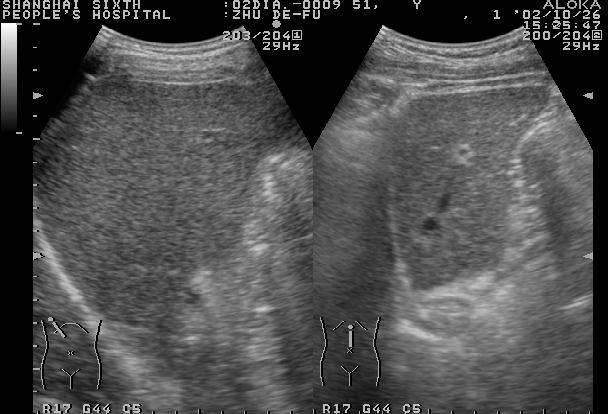

正常肝脏声像图:左图为肝右叶肋间切;右图为肝左叶剑下纵切

正常肝实质显示中等回声,光点稀疏、细微、分布均匀,肝内管道系统走行正常,纹理清晰。

肝包膜因含有纤维结缔组织, 肝膈面包膜光滑呈纤细的强回声。肝左叶边缘锐利左下缘角在35~45°之间,右下缘稍钝圆,80°以内。肝与右肾之间有明显的强回声分界。